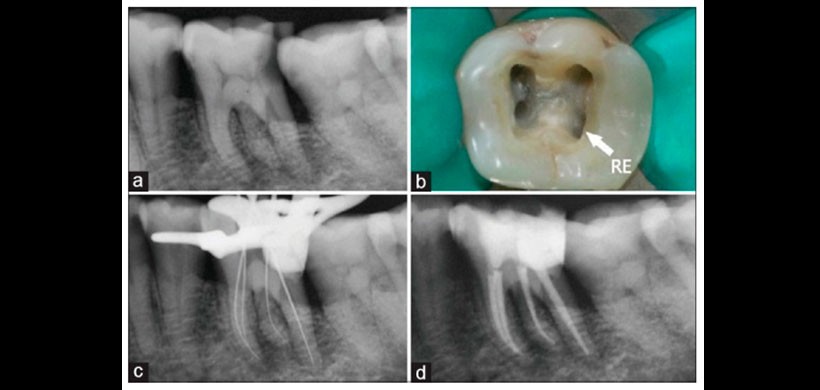

El presente caso clínico describe un primer molar inferior con RE sometido a tratamiento endodóntico con tres raíces: una mesial (con un conducto mesio vestibular y otro mesio lingual), una distal (con un conducto) y otra raíz disto lingual: radix entomolaris (con un conducto).

Figura 5: Tratamiento de conducto de la pieza 3.6 que presenta una raíz supernumeraria. A) Radiografía inicial, b) Visualización de la entrada de los conductos, c) Longitud de trabajo, d) Radiografía final.